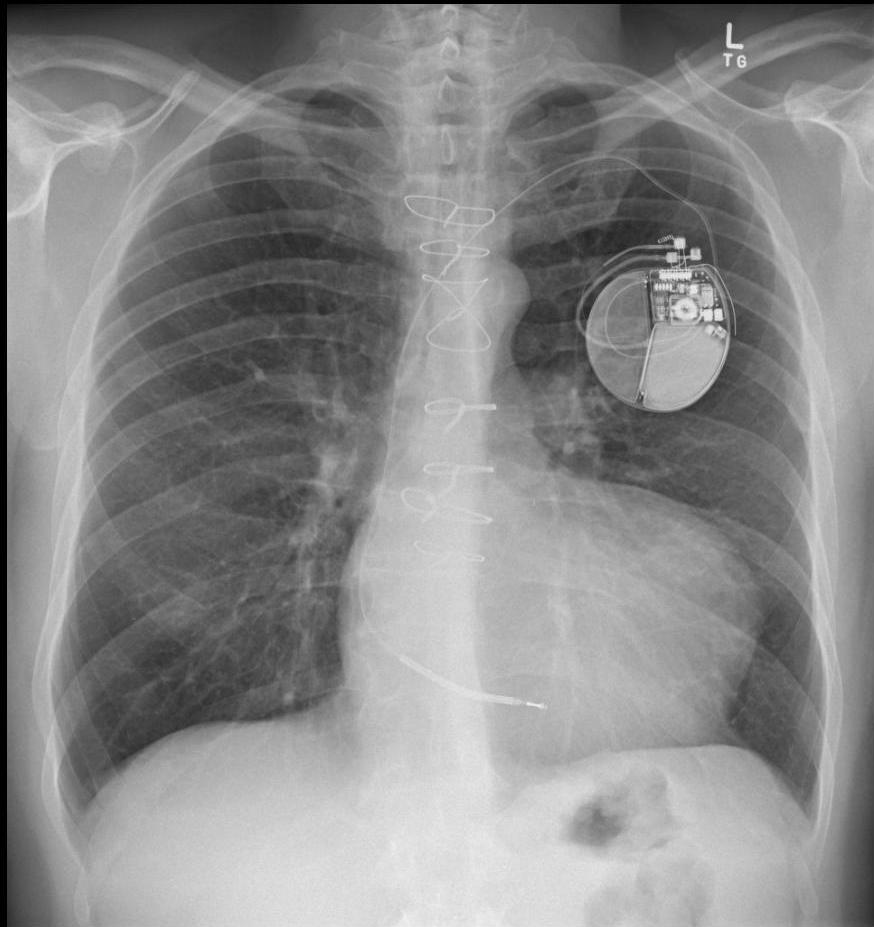

This Photo by Unknown Author is licensed under CC BY-SA NC

Initial Approach

CC BY-NC

This Photo by Unknown Author is licensed under CC BY SA